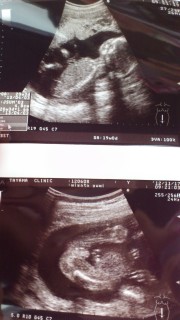

36歳。4人目の妊娠で双子ちゃんです。ワオ(*゚▽゚*) 19週の健診で女の子と言われた時のエコーです。

(左:)先生にはこっちを見ていて写真が写りよくて、可愛いと言われました。もう既に愛おしいです。全身写ったカメラ目線な貴重なエコー写真です。

(右:)この日先生に性別を教えていただきました。 股を下から見たエコー写真です。股と股のあいだにぽっこり。男の子です^^